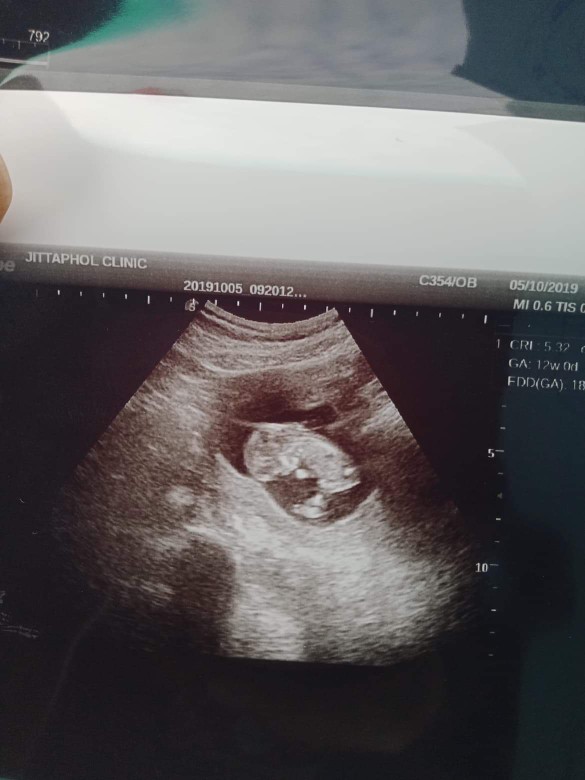

แม่ๆบ้านใหนคลอดเดือนมีนาคมเมษายนบ้างค่ะ ขอดูภาพอัตตราซาวหน่อยจ้าว่าโตแค่ใหนแล้ว